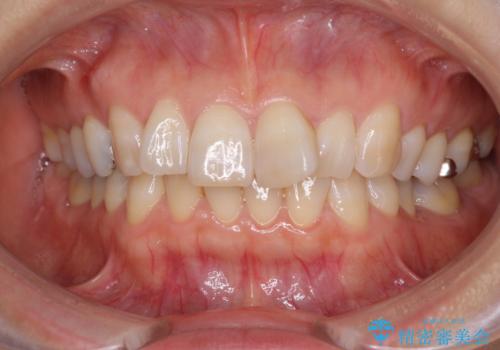

- 前歯のデコボコと上下正中のずれを気にして来院された患者様です。

下顎骨が骨格的にずれがあったため、しっかりと正中を合わせるとなるとワイヤー矯正が必要でしたが、マウスピース矯正を希望されたため、極力正中を合わせることを目標に、インビザラインにて矯正治療を行うこととしました。